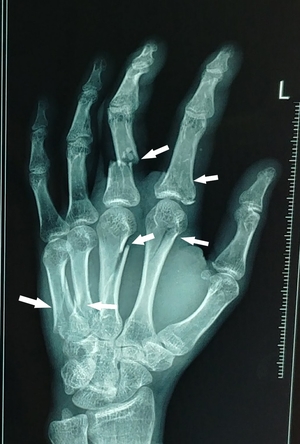

Fractures marked with arrowheads.

Fractures of hand - Dr Nilesh Darawade

Fracture is break in continuity of bone. Most commonly this happens due to trauma although in certain diseases bone may break without any apparent ...